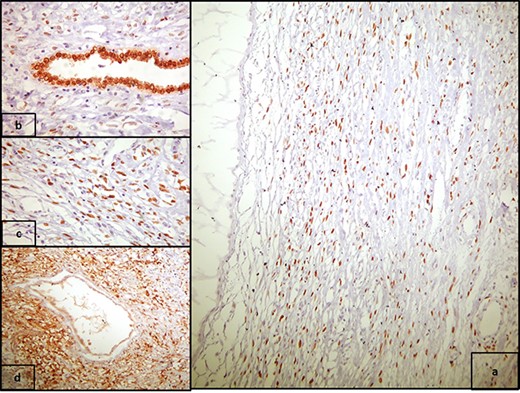

A 20-year-old Caucasian woman presented herself to the outpatient department because of a mass on the left kidney. The mass was an incidental finding in an abdomen computed tomography (CT), which was suggested within the diagnostic evaluation for a persistent flank pain. In the past, she never had any pathologic urologic situation. According to the CT finding, the mass was located on the lower pole of the left kidney (83 × 111 × 111mm) and there was no other pathologic finding. Anamnestically, she had heterozygous beta Mediterranean anaemia. The patient was obese (body mass index = 33.4 kg/m2). We proceeded with a thorax CT which revealed no pathology. The patient underwent a laparoscopic nephrectomy by an urologist well trained and experienced in laparoscopy. Macroscopically, a mass in the lower pole of the left kidney (110 × 100 × 100 mm) was documented. Cut sections revealed multiple thin walled, non-communicating cysts of varying sizes with smooth lining without solid component. Microscopically, the tumor was characterized of cysts separated by thin septa. The cysts lined by single layer of flat, cuboidal and hobnail epithelium and the septa were fibrous, hypocellular to hypercellular. No mitoses or necrosis were identified. The immunohistochemical examination showed that the epithelial cells were positive for the cytokeratins AE1/AE3 and PAX-8. The stromal cells were positive for the progesterone receptors, estrogen receptors and CD10. The latter was concentrated around epithelial elements (Figs 1 and 2). These findings established the diagnosis of ACN. At the 12-month follow-up control with abdomen CT, there was no pathologic finding (Fig. 3). The patient is under urologic and nephrologic montitoring without any abnormal finding at 21 months after surgery. This research complies with the guidelines for human studies and was conducted ethically in accordance with the World Medical Association Declaration of Helsinki.

Postoperative follow-up imaging with abdomen CT at 12 months; coronal (upper side) and axial (lower side) planes, and no evidence of local recurrence, and no other pathologic finding.